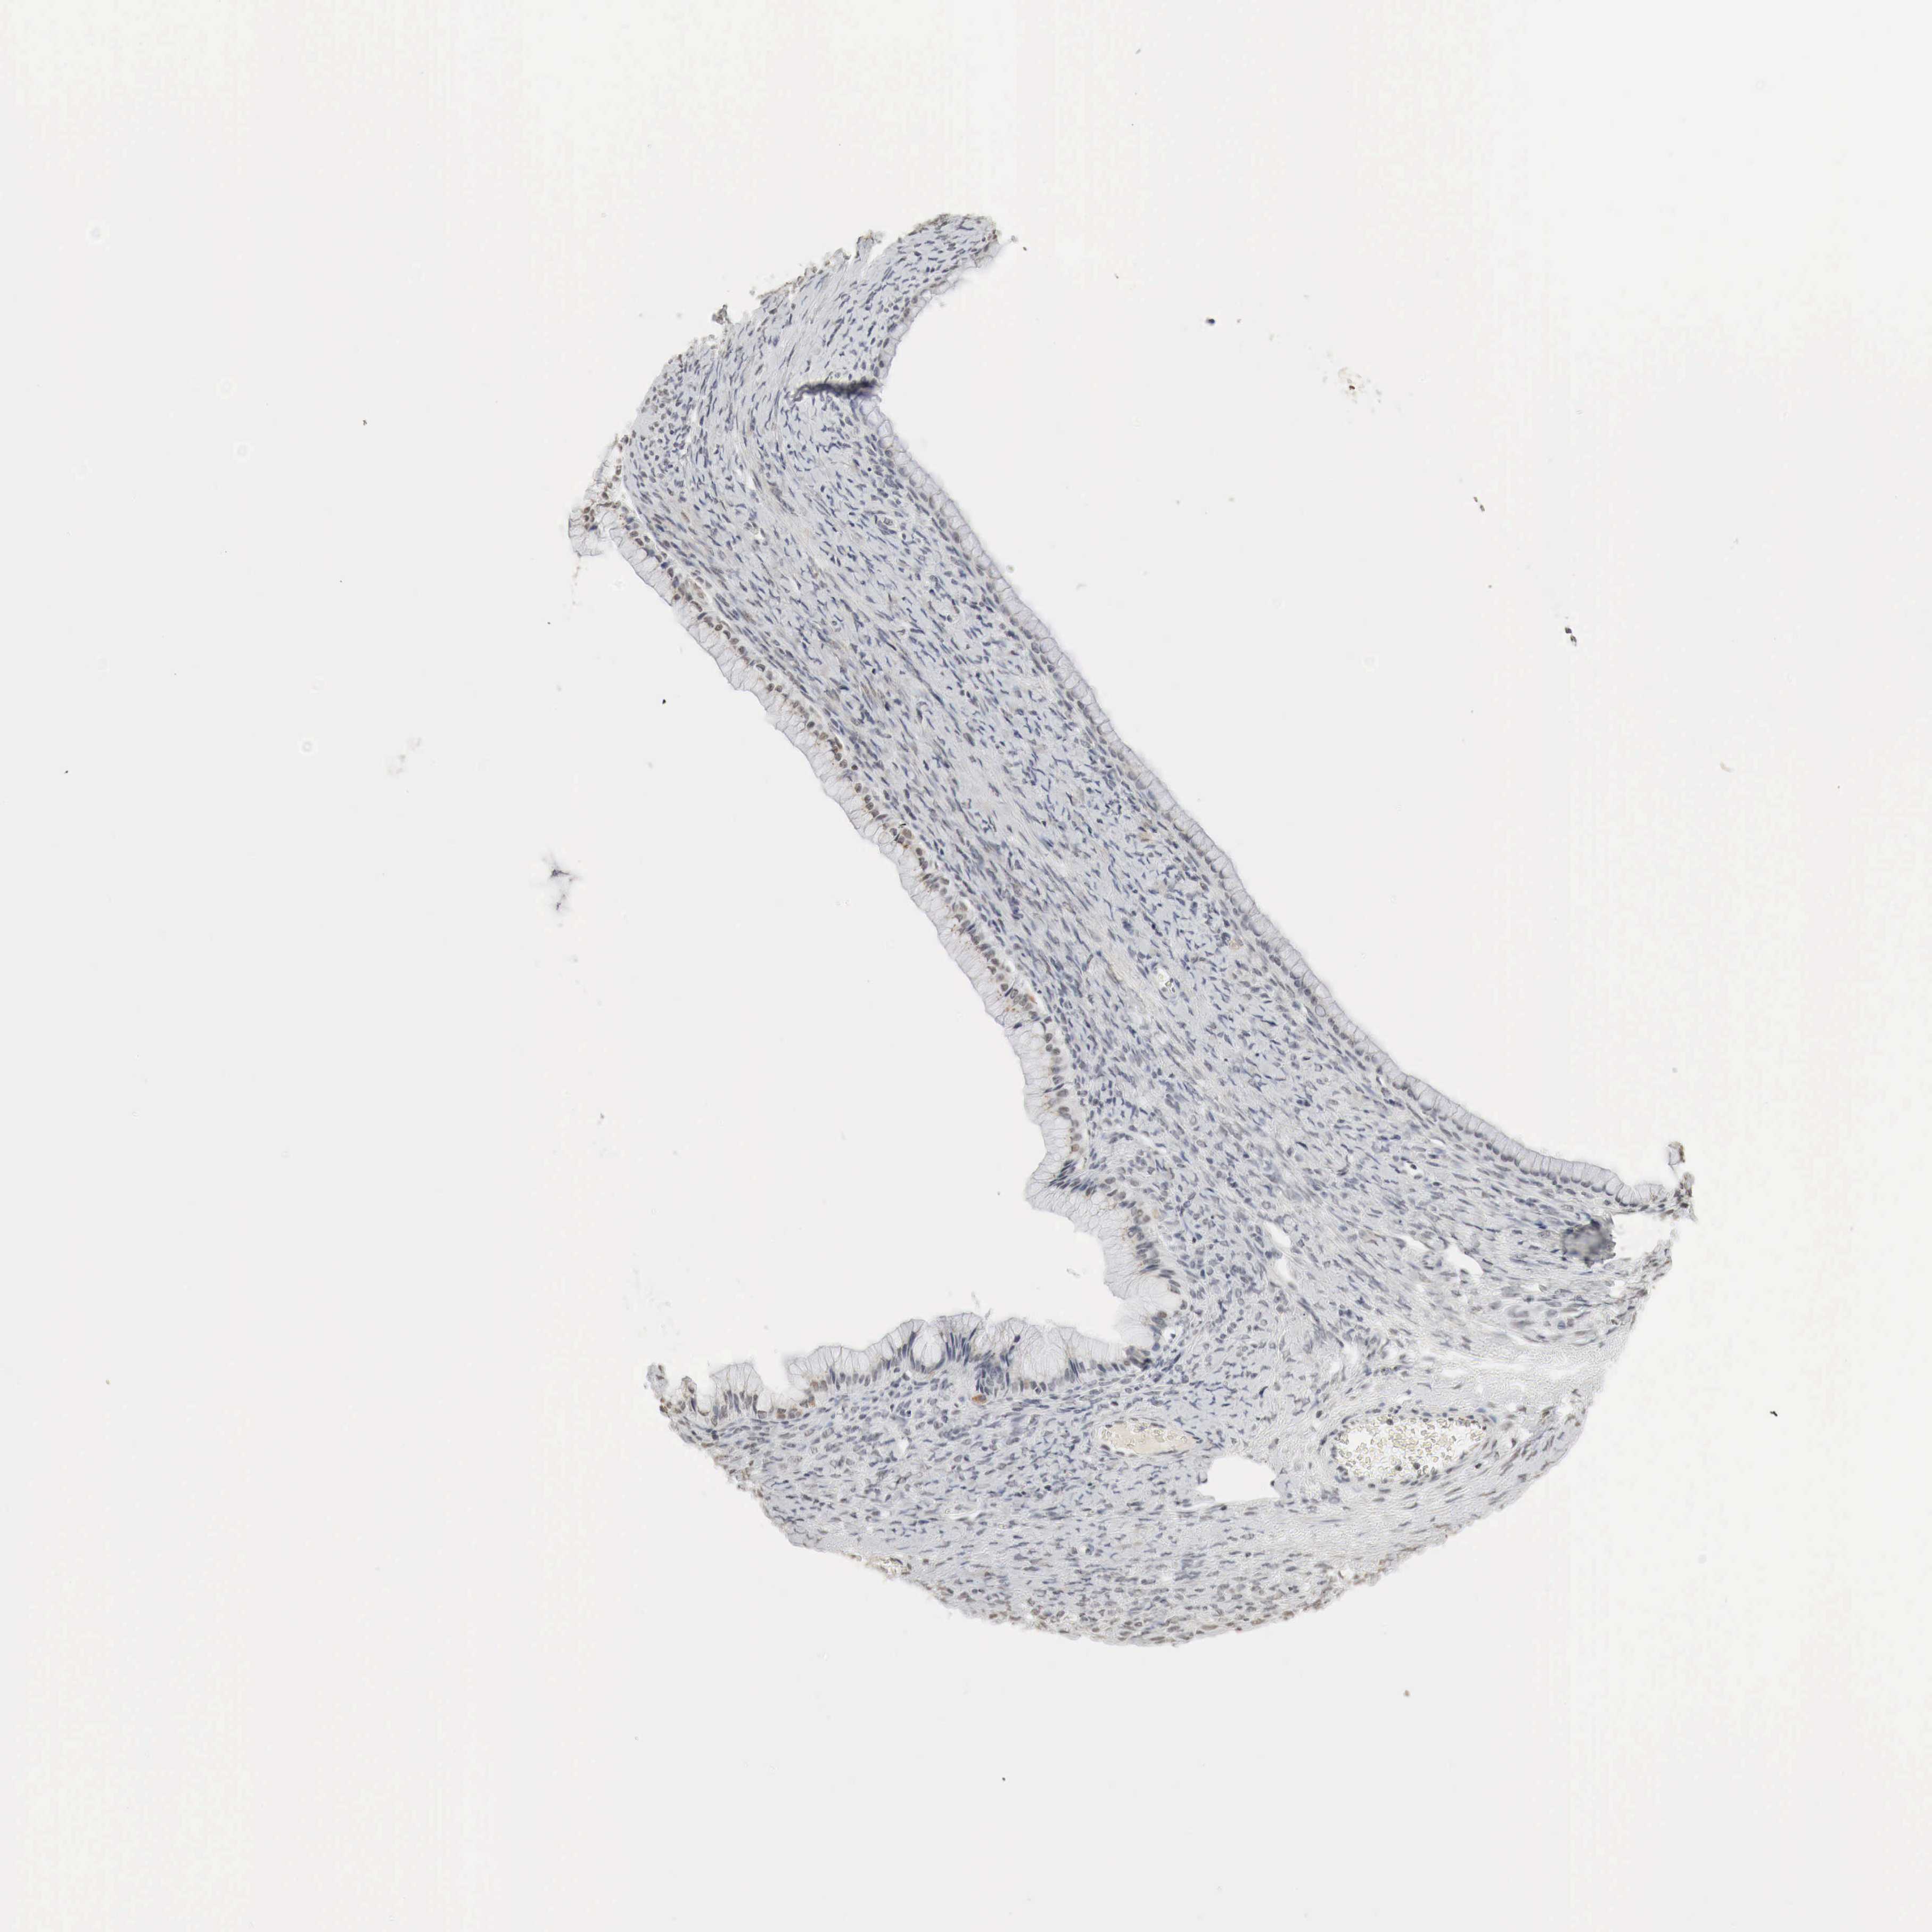

OVARIAN CANCER - Protein expressioni

A mouse-over function shows sample information and annotation data. Click on an image to view it in a full screen mode. Samples can be filtered based on level of antibody staining by selecting one or several of the following categories: high, medium, low and not detected. The assay and annotation is described here.

Antibody stainingi

Antibody staining in the annotated cell types in the current human tissue is reported as not detected, low, medium, or high, based on conventional immunohistochemistry profiling in selected tissues. This score is based on the combination of the staining intensity and fraction of stained cells.

Each image is clickable and will lead to virtual microscopy that enables deeper exploration of all samples and also displays staining intensity scores, fraction scores and subcellular localization as well as patient and tissue information for each sample.

Antibody HPA012016

Antibody CAB000276

Antibody CAB025522

Cystadenocarcinoma, serous, NOS

Carcinoma, endometroid

Cystadenocarcinoma, mucinous, NOS

Carcinoma, NOS